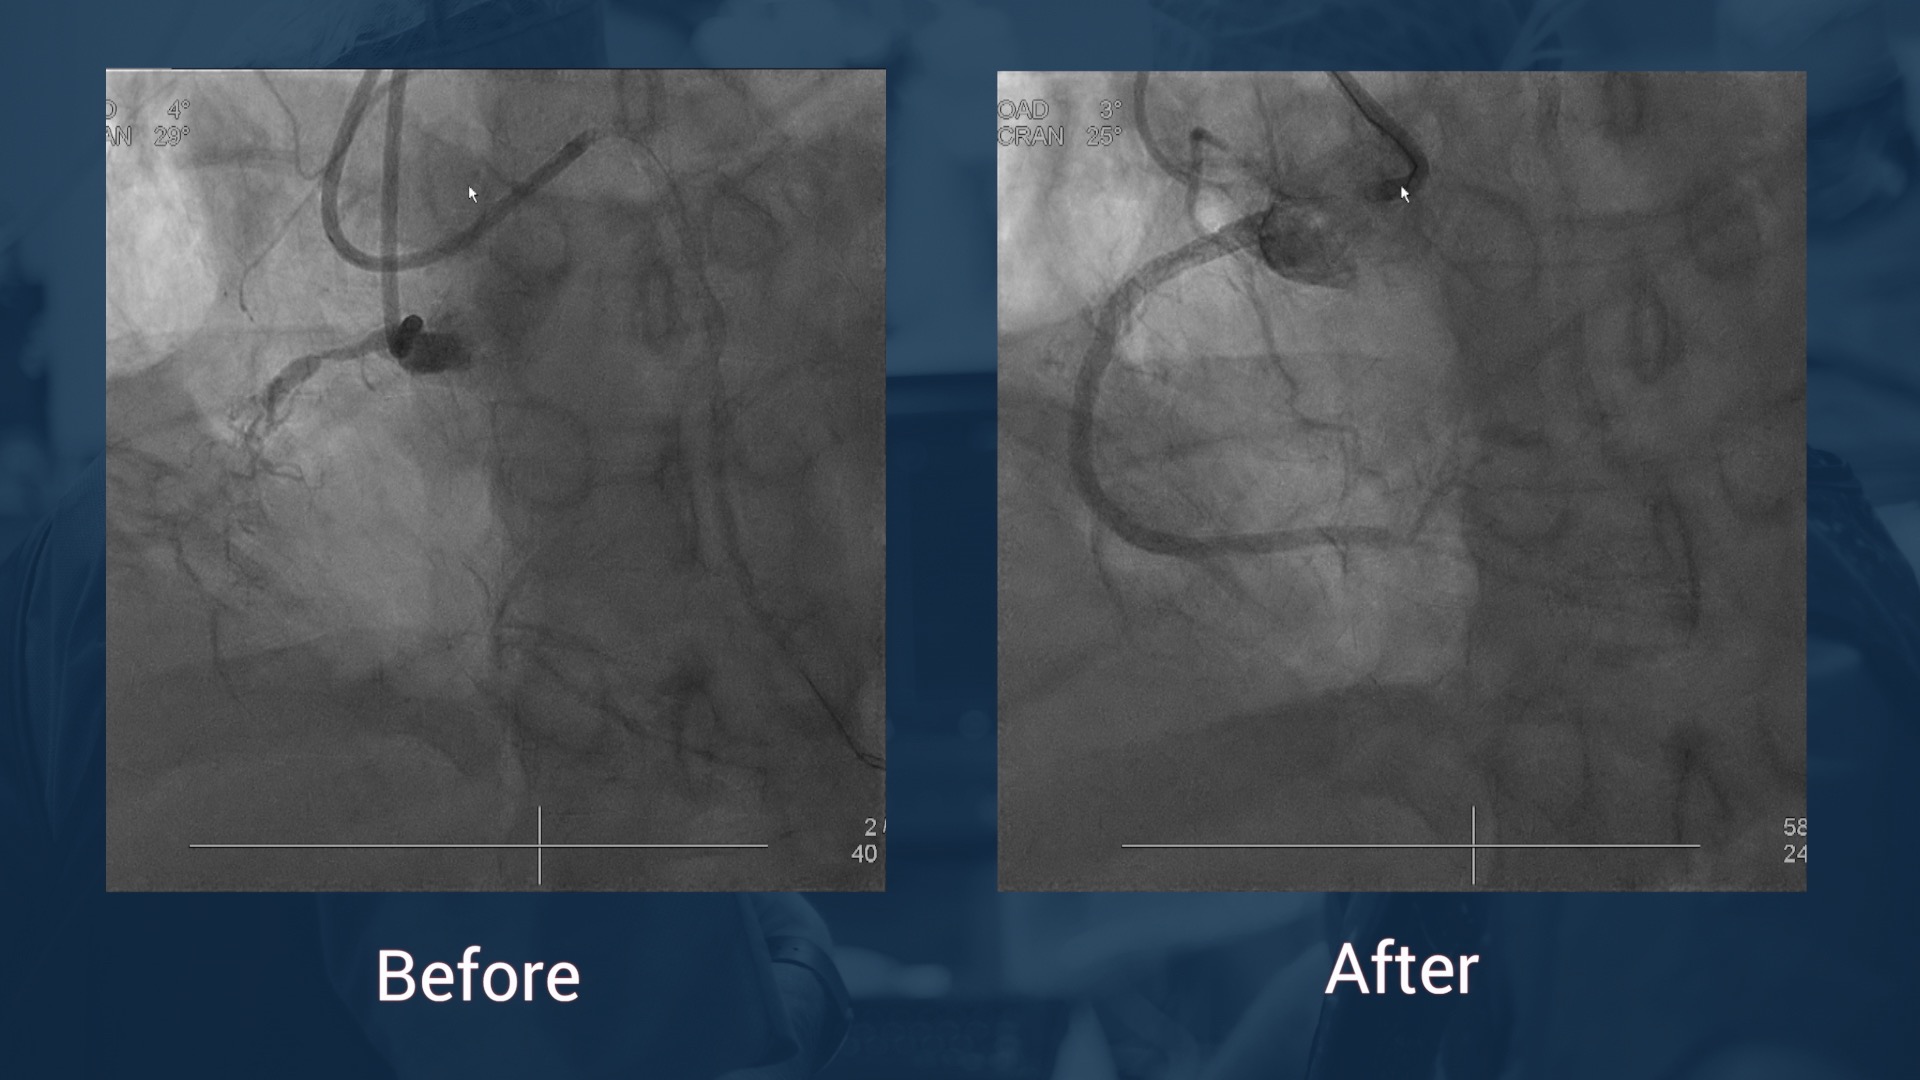

• Coro:  chronic total coronary occlusion of the right coronary artery,significant stenosis of the PDA, significant stenosis of the distal left main trunk ant of the proximal LAD